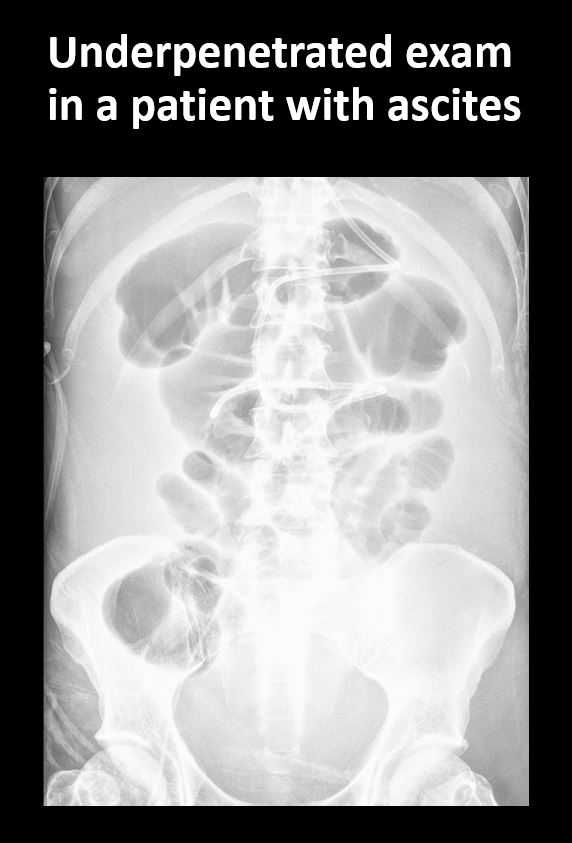

49 year old male with emesis, nausea, post-op.Exam

The exam is technically correct (not over or under penetrated, the entire abdomen/pelvis is covered, the region of interest is covered, and the exam is not limited by overlying structures of soft tissues, body habitus, patient positioning, artifact, or motion). |

No | NA |

The right or left psoas muscle is obscured. |

Yes | NA |

There is free air beneath the diaphragm. |

There is air on both sides of the bowel wall (Rigler's sign). |

There are distended loops of small bowel with some gas in the colon which could be from partial or early obstruction, less likely adynamic ileus in this post-op patient. Free air could be secondary to recent surgery.

Notify the clinical team verbally and immediately about findings regarding dilated small bowel, free air, and need for follow-up, to assess for possible obstruction vs adynamic ileus.

Urgent: non-routine communication